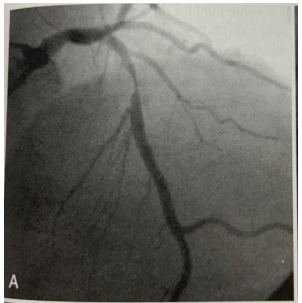

Paciente homem, 57 anos, previamente hipertenso, diabético,

tabagista, com dor retroesternal em caráter de queimação,

irradiando para membro superior esquerdo, iniciada em repouso

há 30 minutos, atenuada parcialmente após uso de dinitrato de

isossorbida. Durante o atendimento no prontoatendimento,

troponina ultrassenssível com curva enzimática positiva.

Durante a internação realizou cineangiocoronariografia:

BRAUNWALD. Tratado de Doenças Cardiovasculares. 9ª Ed. Fig. 58-10; pág.1309.

O diagnóstico e a artéria acometida são, respectivamente.